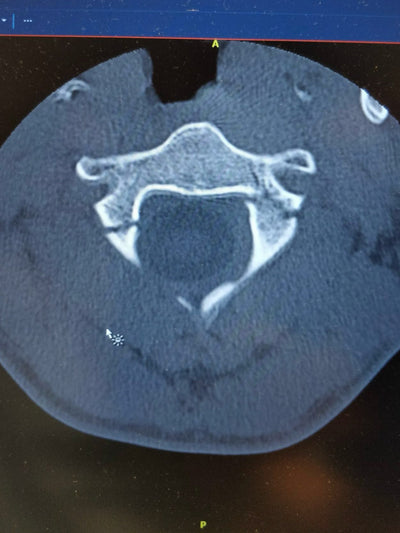

As soon as they saw the scan results, there was a sense of panic: My cervical vertebra C2 was fractured and I had to be hospitalized immediately.